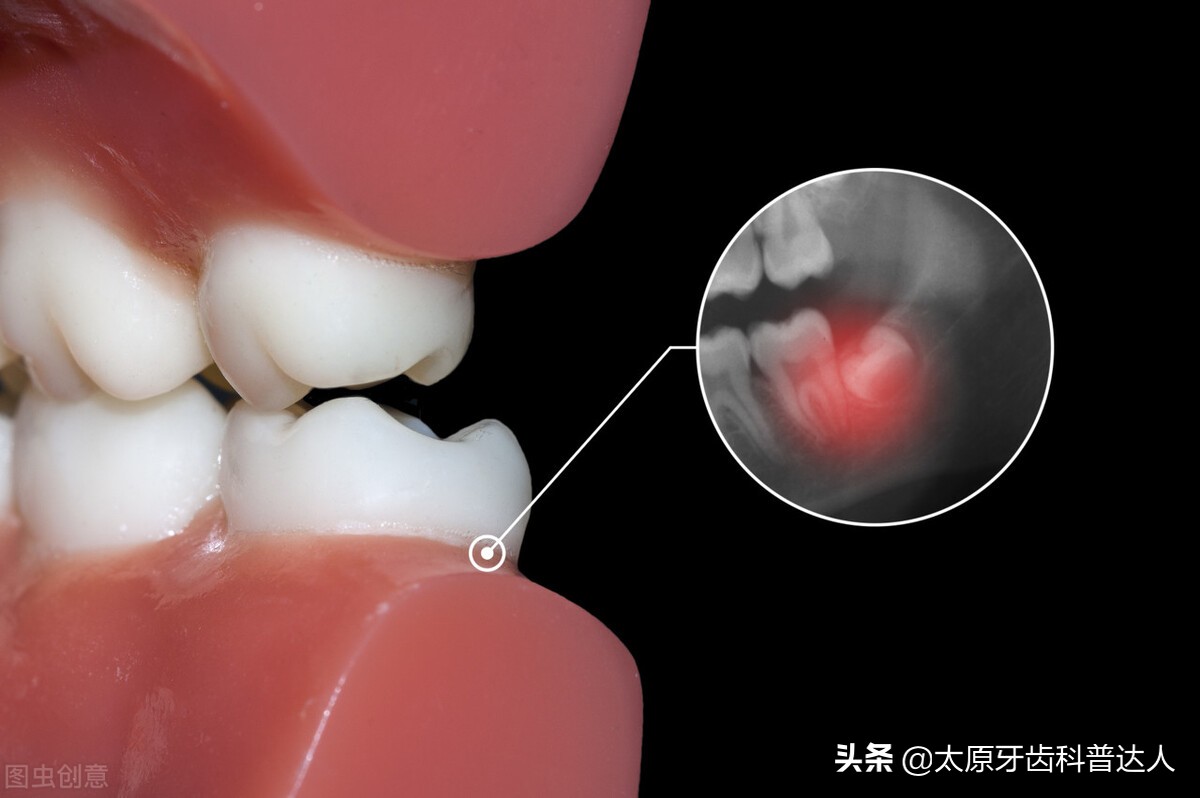

4、智齿冠周炎。由于阻生智齿萌出空间不足,容易引起智齿冠周软组织发炎,即智齿冠周炎。智齿冠周炎的主要症状包括牙龈肿痛、颊部肿胀、张口受限、吞咽困难等,严重者还伴有全身不适、头痛、发热、畏寒等。

解决方法:智齿冠周炎需先进行消炎处理,待炎症控制之后,尽快拔除智齿。